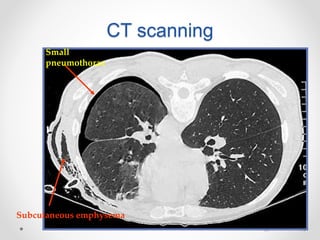

CT scanning

 It is recommended in difficult cases such as

patients in whom the lungs are obscured by

overlying surgical emphysema

 To differentiate a pneumothorax from suspected

bulla in complex cystic lung disease

Small

pneumothorax

Subcutaneous emphysema